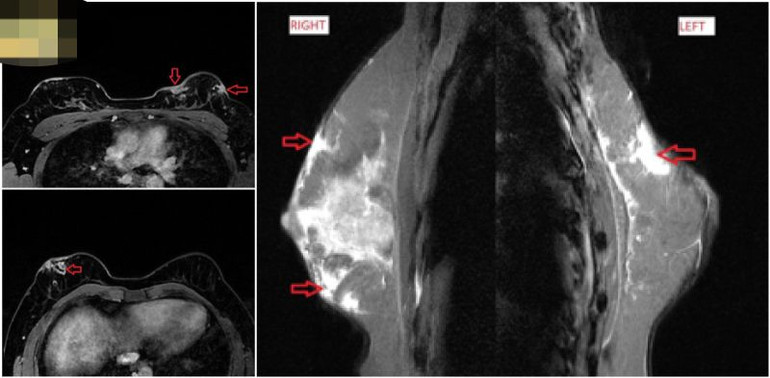

Chị V. đến Medlatec khám trong tình trạng đau, sưng nề, mưng mủ trầm trọng hai bên ngực. Kết quả siêu âm và chụp cộng hưởng từ của bệnh nhân cho thấy hình ảnh các ổ dịch viêm, áp xe rải rác tuyến vú hai bên. Đồng thời, bệnh nhân được chọc dịch ổ áp xe lấy mẫu bệnh phẩm xét nghiệm, kết quả dương tính với vi khuẩn NTM. Bác sĩ chẩn đoán xác định chị V. nhiễm trùng da mô mềm do vi khuẩn Mycobacterium fortuitum - một loài vi khuẩn lao không điển hình (NTM).

| Biến chứng thẩm mỹ sau tiêm mỡ tự thân. |